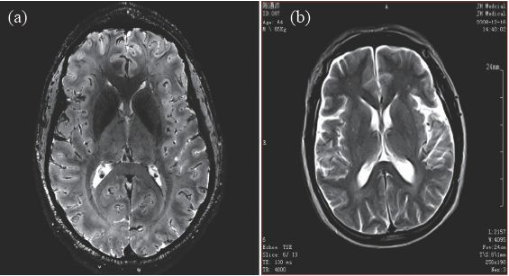

因此,磁共振成像技術(shù)目前的發(fā)展趨勢(shì),是朝著更高磁場(chǎng)強(qiáng)度發(fā)展,以期獲得更高分辨率的圖像,并實(shí)現(xiàn)多核成像。圖6 顯示了磁場(chǎng)強(qiáng)度的高低對(duì)圖像分辨率的影像,(a)為7 T 磁場(chǎng)下的圖像,(b)為0.35 T磁場(chǎng)下的圖像,二者的圖像分辨率可見一斑。

image.png

圖6 T2 加權(quán)成像(a)7 T 下的成像,分辨率約0.3 mm;(b)0.35 T下的成像,分辨率約1 mm